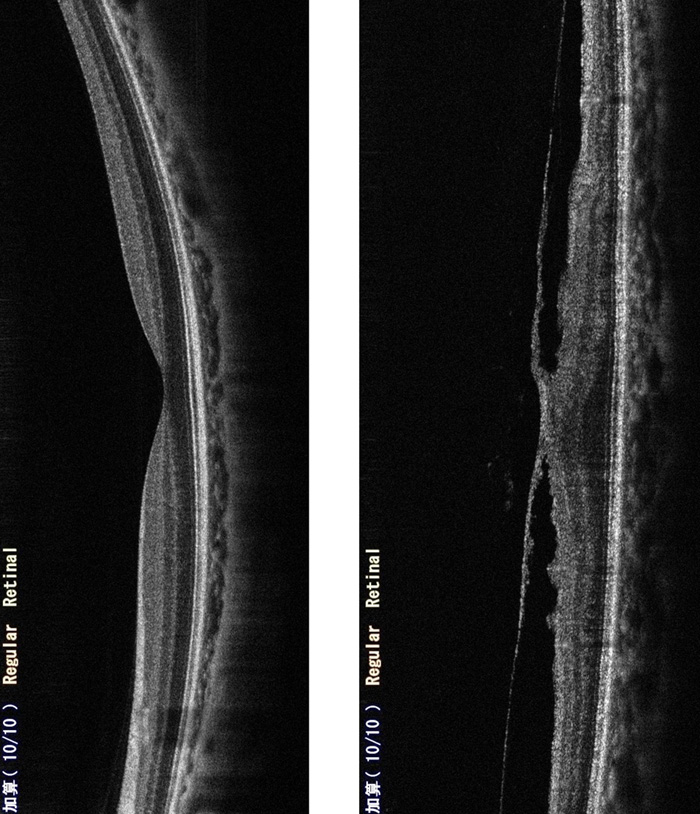

【写真左】OCTによる網膜の正常網膜の断層結果:網膜の表面は平滑で、すり鉢状に滑らかに凹んだ黄班部が明瞭にわかります。

【写真右】黄班前膜の断層結果:網膜表面上に膜が形成され(黄班前膜)、引きつられた形となり、黄班部の滑らかな凹みが消失しているだけでなく、隆起しているのが判ります!。その為に「像が歪んで見える」等の症状が出ます。